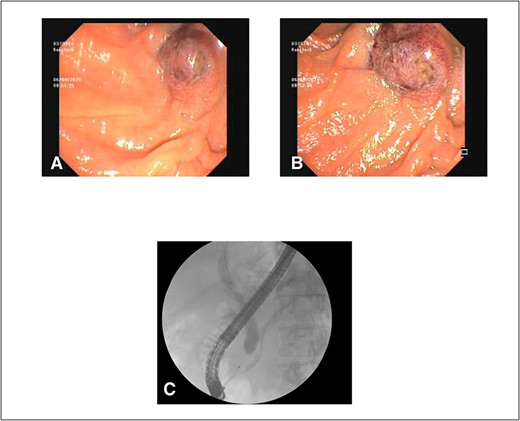

After consultation with our Hepatobiliary service, the consensus was for the patient to undergo an urgent ERCP. Intraoperatively, a duodenoscope was introduced through the mouth and was advanced to the duodenum at the ampulla of Vater. The major papillae were bulging and a malignant appearing infiltrative mass was visualized. A tapered tip cannula was inserted through the ampulla and contrast was injected, revealing a patent PD and a single 18-mm long stenosis of the distal third of the CBD with significant dilatation of the proximal CBD and intrahepatic ducts (Fig. 2). A 10Fr 7-cm transpapillary plastic stent was inserted with a single internal flap, 5.5 cm, into the CBD. The biliary pancreatic junction was biopsied with cold forceps for histology. Cholangiopancreatography revealed the stent was in good position with good flow of contrast into the duodenum beyond the filling defect (Fig. 3).

(A) and (B) malignant appearing soft tissue infiltrative mass within the ampulla of Vater seen on ERCP; (C) cholangiopancreatography showing stenosed distal third of the common bile duct along with a patent pancreatic duct.